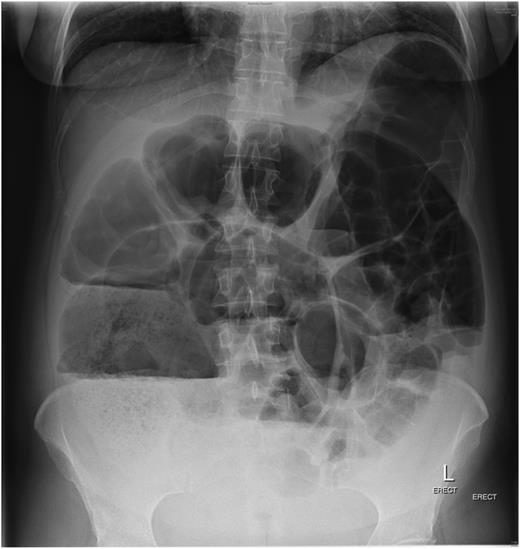

The patient, a 34-year-old female, developed symptoms consistent with pseudo-obstruction on Day 3 post-emergency Caesarean section, which was performed for foetal distress and possible placenta abruption. An abdominal X-ray was performed which showed a significantly dilated colon (Fig. 1), and the diagnosis of pseudo-obstruction was again confirmed on computer tomography (CT) scan of the abdomen which showed a caecum measuring 9.8 cm transversely (Fig. 2). Emergency colonoscopic decompression with the insertion of a flatus tube was performed and medical management, including cessation of opioids, anticholinergics and correction of electrolyte abnormalities, was commenced.

CT scan of the abdomen showing caecum measuring 9.8 cm transversely.